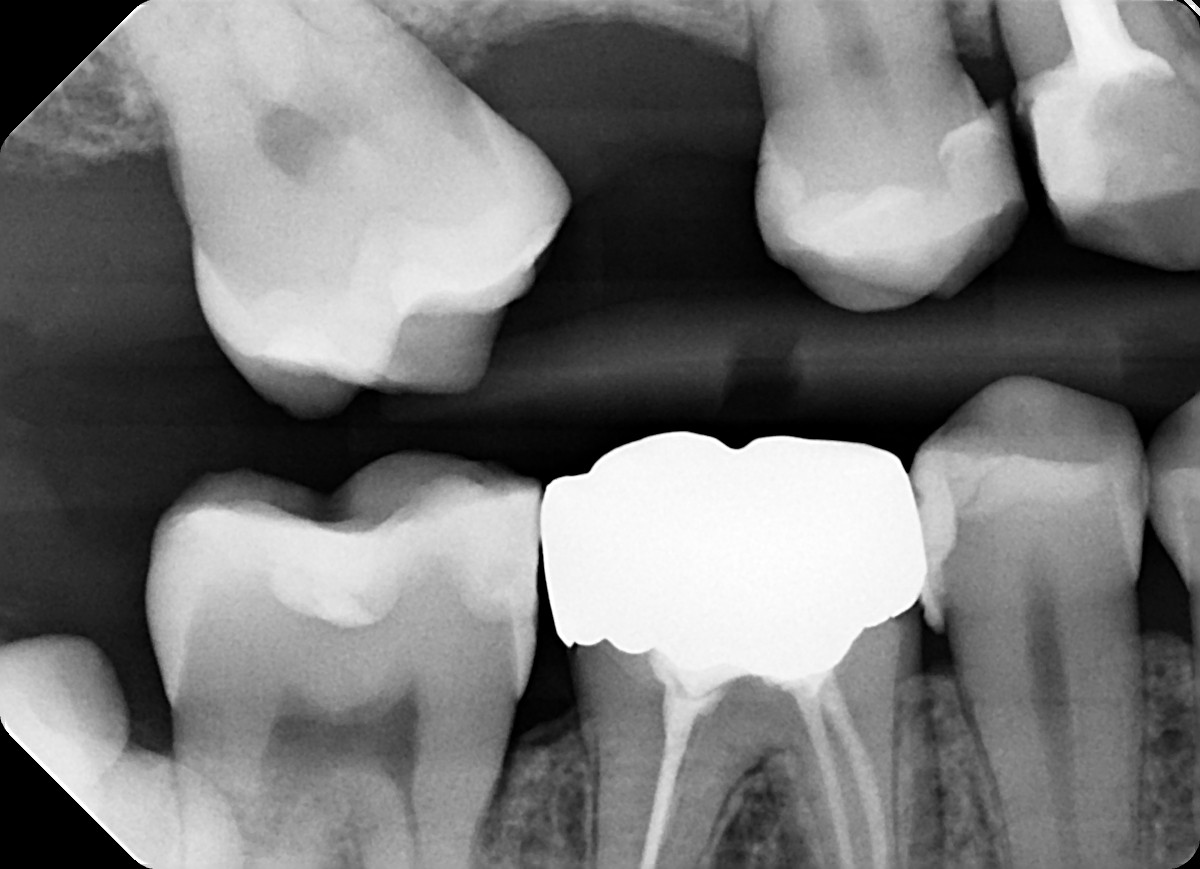

1.  In the X ray bellow for which jaw periodontal bone loss is evident?